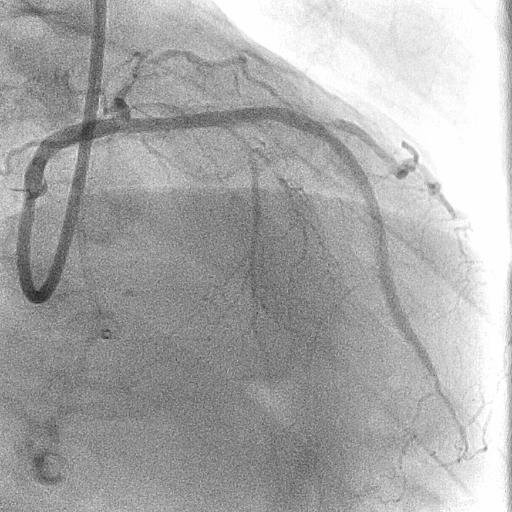

The procedure began via right and left femoral arteries using Launcher 8F EBU3.5SH and 7F SAL0.75SH guiding catheters. Zizai 150 cm and Corsair Pro 135 cm microcatheters were used. An antegrade approach with wire escalation from SION to XT-A and Conquest Pro 8-20 was attempted. SION and a 2.5¡¿15 mm Ryurei balloon were used as anchors, but a heavily calcified ¡°full moon-like¡± distal LAD lesion could not be crossed. GUIDEPLUS 5F with a 2.5¡¿15 mm Ryurei enabled guide extension lock, though attempts with Ryurei 1.0¡¿5 mm and Mogul SP Thinner 1.5F failed. Using SASUKE 145 cm, Gladius EX was redirected into the subintimal space via Corsair Pro and a 2.25¡¿15 mm Ryurei. ELCA (0.9 mm) and PTCRA with FINECROSS MG and Mogul SP Thinner were unsuccessful as the RotaWire could not cross. Subsequent ballooning with Ryurei 2.25¡¿15 mm and Hiryu Plus 2.5 mm was performed. ADR using Caravel MC and Conquest Pro 12ST achieved true lumen re-entry, followed by stenting with GUIDEPLUS II ST 6F and DESs.

It was one effective option for CTO PCI with severely calcified lesions accompanied by full moon-like calcification using HydroDynamic contrast Recanalization followed by Tip-detection Antegrade Dissection Re-entry method.